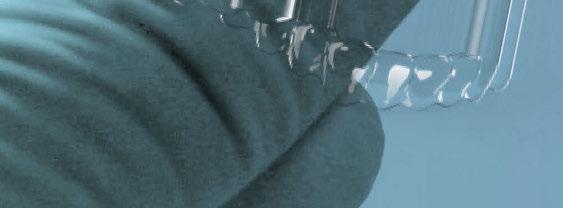

Los implantes estaban fabricados con una aleación de vitalium y requerían dos procedimientos. Inicialmente, una cirugía para realizar una impresión con alginato sobre el hueso y su posterior fabricación en el laboratorio sobre el modelo de escayola, con una adaptación subóptima del IS. En un segundo procedimiento, se acometía la colocación pasiva del implante para su posterior fibrointegración.

OBJETIVOS

La aparición de nueva tecnología de diseño y fabricación asistida por ordenador (CAD/CAM) y el empleo de metales más biocompatibles y con capacidad de osteointegración como el titanio ha permitido revisar esta técnica (6). La posibilidad de realizar tratamiento de superficie para favorecer la integración secundaria ha permitido, además, una adaptación submilimétrica muy precisa al hueso atrófico o remanente (7). Combinada con tornillos de osteosíntesis, la proveen de resistencia mecánica y estabilidad primaria suficiente para tolerar las cargas masticatorias. Los nuevos IS de titanio hechos a medida han vuelto a abrir el debate sobre el tratamiento de los grandes defectos del maxilar, ofreciendo algunas ventajas frente a otros procedimientos reconstructivos más complejos, con menor morbilidad y tiempos de tratamiento más cortos.